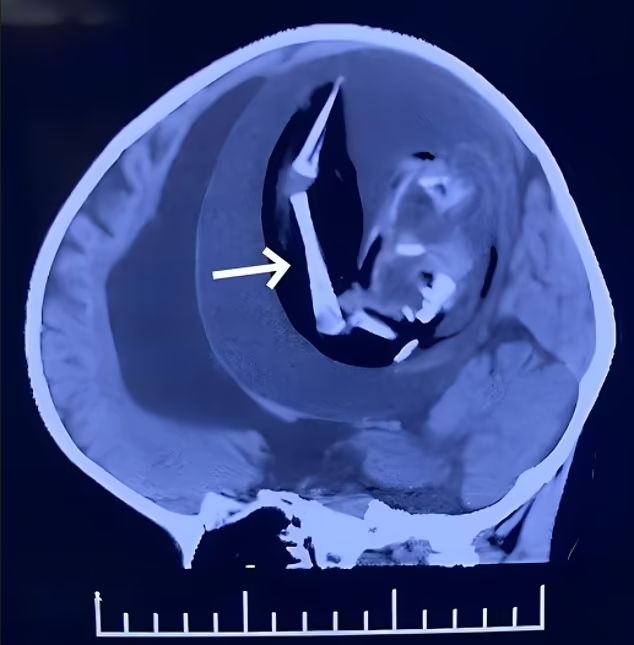

Die Ärzte führten eine CT-Untersuchung ihres Schädels durch, die "Weichteilgewebe, gliedmaßenähnliche Knochen und gemischte Knochengewebeschatten im intrakraniellen Bereich" ergab. Es wurde beschlossen, das Mädchen zu operieren.

Embryo mit Händen und Füßen

"Wir entfernten einen unreifen Embryo mit Organen wie Mund, Augen, fötalem Kopf, fötalem Haar, Körper, Unterarm, Händen und Füßen", schreiben die Autoren des Fallberichts. Der Embryo war 18 Zentimeter lang, er hatte missgebildete Gesichtszüge und Gliedmaßen sowie lange Knochen und eine Wirbelsäule. Leider blieb das kleine Mädchen nach der Operation bewusstlos und starb 12 Tage später, da die Schädigung ihres Gehirns zu schwer war.